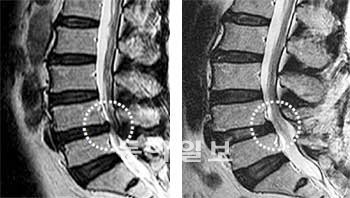

협착증의 치료는 증상의 정도에 따라 보존적 치료와 수술적 치료로 나뉩니다. 대부분의 환자는 보존적 치료로 증상을 개선할 수 있습니다.

보존적 치료로 3개월 이상 호전이 없거나, 진행성 신경 손상, 심한 보행 장애가 있는 경우 수술을 고려합니다. 척추관 확장술(감압술)이 일반적입니다.